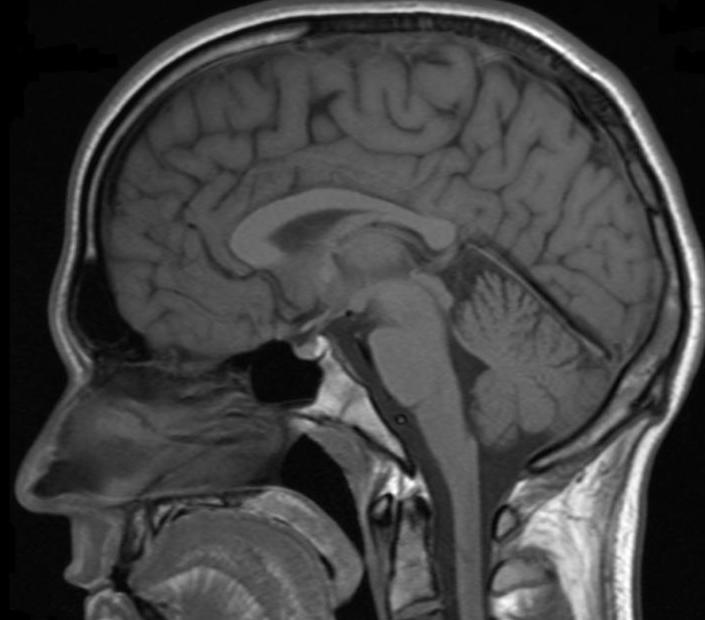

Existe una gran variedad de radiografías como por ejemplo radiografía abdominal, de tórax, de una extremidad, de la mano, de las articulaciones, del cuello, del cráneo, de la pelvis, etc.